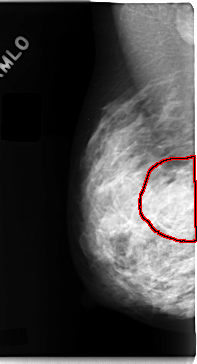

C_0098_1.RIGHT_MLO

FILE: C_0098_1.RIGHT_MLO.OVERLAY

TOTAL_ABNORMALITIES 1

ABNORMALITY 1

LESION_TYPE MASS SHAPE IRREGULAR MARGINS ILL_DEFINED

ASSESSMENT 4

SUBTLETY 2

PATHOLOGY MALIGNANT

TOTAL_OUTLINES 1

BOUNDARY